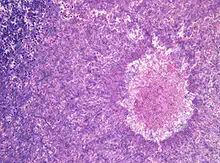

| Aspergillomas complicating tuberculosis: multiple aspergillomas within large cavitary lesions of tuberculous origin. | |

Although most fungi—and especially Aspergillus—fail to grow in healthy human tissue, significant growth may occur in people whose adaptive immune system is compromised, such as those with chronic granulomatous disease, who are undergoing chemotherapy, or who have recently undergone a bone marrow transplantation. Within the lungs of such individuals, the fungal hyphae spread out as a spherical growth. With the restoration of normal defense mechanisms, neutrophils and lymphocytes are attracted to the edge of the spherical fungal growth where they lyse, releasing tissue-digesting enzymes as a normal function. A sphere of the infected lung is thus cleaved from the adjacent lung. This sphere flops around in the resulting cavity and is recognized on x-ray as a fungus ball. This process is beneficial as a potentially serious invasive fungal infection is converted into surface colonization. Although the fungus is inactivated in the process, surgeons may choose to operate to reduce the possibility of bleeding. Microscopic examination of surgically removed recently formed fungus balls clearly shows a sphere of dead lung containing fungal hyphae. Microscopic examination of older lesions reveals mummified tissue which may reveal faint residual lung or hyphal structures.[4]